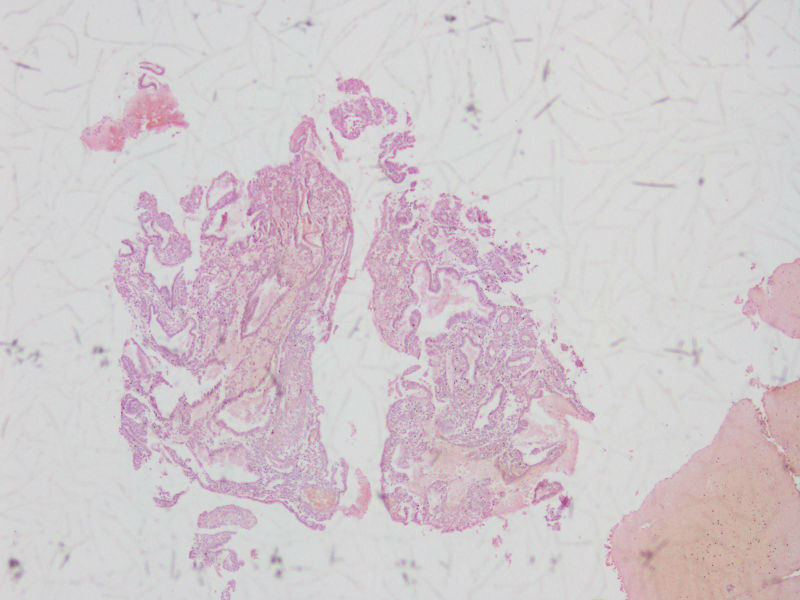

女44,阴道不规则流血一月

流血期宫内膜